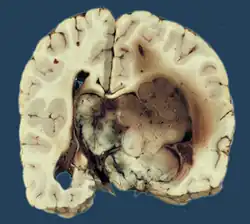

Choroid plexus tumors are divided into three categories by the World Health Organization (2016):[9] papillomas (grade I), atypical tumors (grade II), and carcinomas (grade III). Less than two mitotic figures per 10 high power fields are present in CPPs, two to five are present in atypical ones, and more than five are present in carcinomas. The tumors are visible as pink, soft, spherical lumps with erratic projections and considerable vascularity.

A neurosonogram via the anterior fontanelle will show an echogenic lesion inside the ventricles if the fontanelles are not united. This lesion exhibits bidirectional flow throughout the diastole, demonstrating blood flow via disorganized vascular arrangement. Sometimes ultrasound scans are used to diagnose the lesions before birth.[15] An isodense or slightly hyperdense lesion inside the ventricles, as well as the resulting ventriculomegaly, are visible on computer tomography (CT).[16] The intraventricular lobulated masses are well-defined and resemble fronds; they are hypointense on T1WI and hyperintense on T2WI on magnetic resonance imaging (MRI).[17] Active blood flow is indicated by the presence of flow voids. A rich vascularity gives the lesions a brilliant enhancing quality. Recent researches have shown that choroid plexus papilloma and choroid plexus cancer may be distinguished from one another using arterial spin labeling.[18]